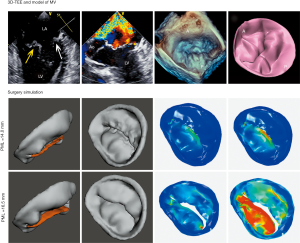

3D digital model

Both the CTA and 3D-TEE DICOM images in 35% R-R interval were derived and imported into postprocessing software, including Mimics 19.0 and 3-matic 11.0 (Materialise, Leuven, Belgium). The CTA image data were segmented to create the digital model of the left heart cavity while the 3D-TEE data were postprocessed to exactly recreate the MV structure. Threshold segmentation is mainly used in data post-processing. The range of threshold is set at 180–850 HU in the CTA image, and the 3D mask (mask) of the left heart cavity can be obtained using the CT heart function in the software. The range of threshold was set at 70–240 HU in the 3D-TEE image to exactly recreate the MV structure. Points on the mitral annulus with small movement were marked as registration points, and the two different modes of cardiac imaging were fused. Finally, a 3D digital model of the left heart system, including left atrium (LA), LV, aorta (Ao) and MV, was obtained using the fusion method (Figure 1). It was saved in STL format after smoothing and noise reduction. Mitral annular calcification was segmented by raising the value of the threshold and then saved separately in STL. After being printed, the calcified section was combined with the silicone valve model for integration into a whole model.

Surgical simulation was performed using both the dynamic 3DP model and CFD. For the dynamic 3DP model, two experienced cardiothoracic surgeons were invited to perform MVR with the same-sized annuloplasty ring as used in patients; meanwhile for CFD simulation, different digital models of annuloplasty rings with diameters from 26 to 38 mm were designed using 3-matic. The simulation of MVR was accomplished using Meshmixer software (Figure 5).

Of the 21 patients who were transferred to mitral replacement, there was one with Barlow disease (BD). The MV leaflets were redundant, with prolapse of P2 and P3. 3D-TEE showed billowing of both AML and PML, especially the P3 segment. Color Doppler showed severe MR originating from the PML. One challenge of repairing BD mitral valves is the development of postoperative SAM of the AML, which is often associated with a tall PML. As the height of the PML increases, the coaptation point gets closer to the base of the AML, and the length of the AML beyond the coaptation point (residual length) increases. Residual AML is free to move in response to the drag created by the jet flow, which can cause SAM and LVOT obstruction. We simulated the procedure with different PML lengths from 14.0 to 19.0 mm (with an 0.5 mm increase on each attempt). The residual length of the AML ranged from 2.8 to 5.4 mm (Table 5). The results show that SAM and LVOT obstruction occurred when the PML length reached 16.5 mm, with a residual length of the AML at 4.2 mm (Figure 8). The pressure gradient at the LVOT reached 17.2 mmHg after repair, but was only 6.8 mmHg before surgery.